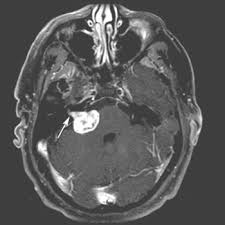

听神经瘤也叫“前庭神经鞘膜瘤”,是起源于前庭神经鞘膜的一种【良性】肿瘤,占颅内良性肿瘤的6%-8%,占桥小脑区肿瘤80%-90%。

其次,随着瘤体增大,可以因为压迫其他邻近的神经出现相关症状,例如压迫三叉神经出现同侧面部的感觉迟钝和角膜反射减退;压迫小脑出现精细运动,协同运动障碍。

但最重要的,还是压迫与其相邻非常近、共同进入内听道的面神经,导致面瘫。而很多患者的首发表现也是面瘫,这也导致听神经瘤与面神经瘤的鉴别非常困难,只有通过手术切下来以后才知道,这个肿瘤是来源于听神经还是面神经。

尽管如此,听神经瘤是一种生长缓慢的良性肿瘤,每年大概也就长大0.25-0.4cm,只有少数会在一年内迅速增大。